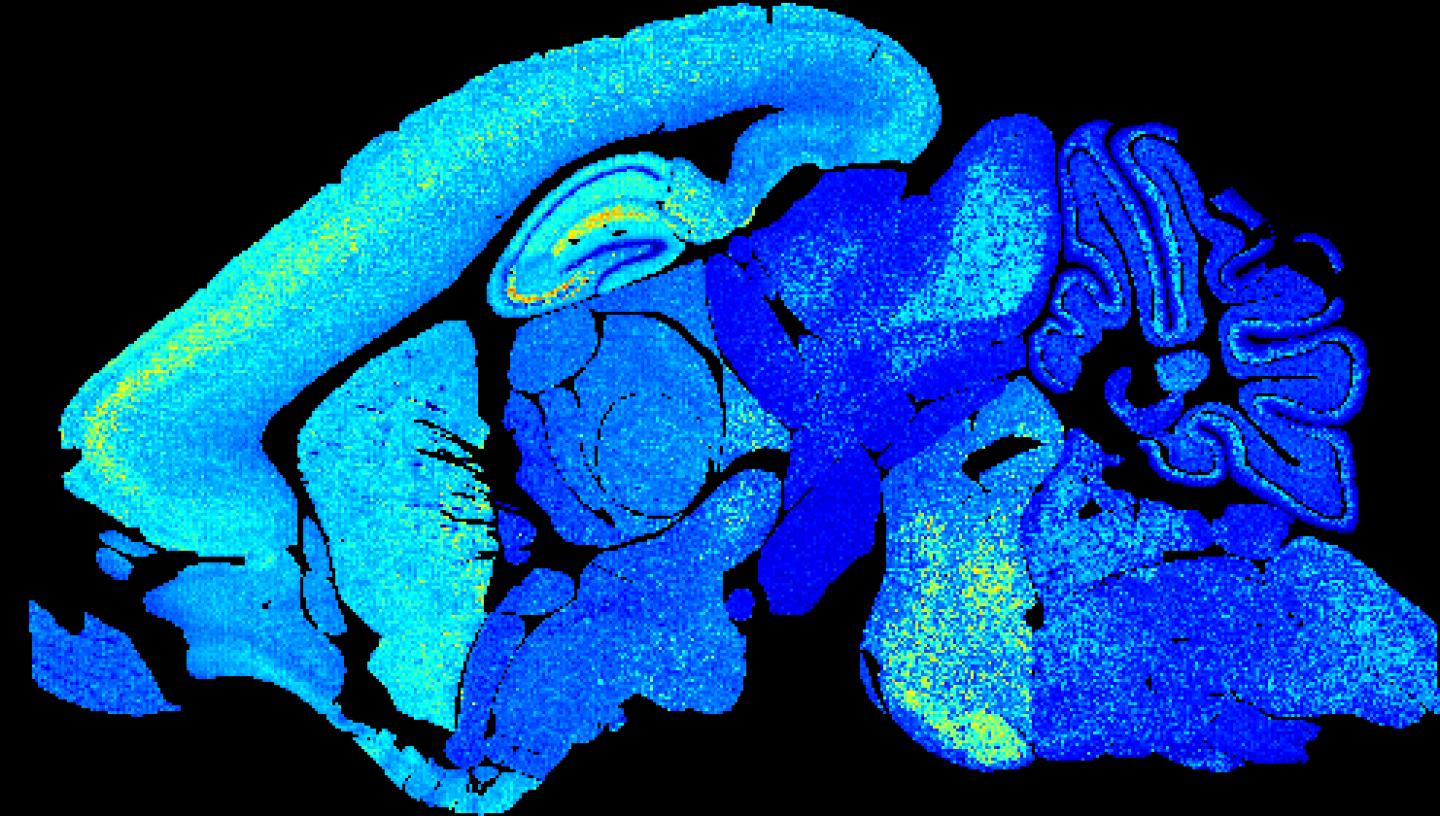

image: Young mouse brain section showing lower synapse diversity. Credit Zhen Qui and Seth Grant University of Edinburgh.

The colourful pictures of the whole mouse brain at different ages are the first of their kind and a pivotal step forward in understanding behaviour, scientists say.

The images are of synapses - vital connections that carry electrical and chemical messages between brain cells. Synapses store memories and synapse damage is linked to more than 130 brain diseases.

Researchers based at the University of Edinburgh colour-coded the different types of molecules to highlight the range of synapses in mouse brains from birth to old age.

Images from middle-aged brains burst with colour, illustrating a wide variety of synapses. Both very young and very old brain show less synapses and less complexity.